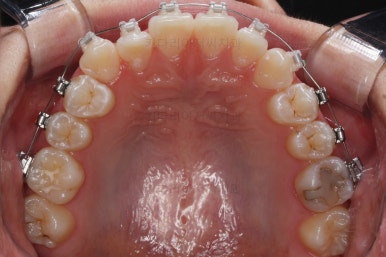

장치를 부착한 직후츼 사진입니다.

장치를 따라 걸려있는 철사의 형태를 보면 생각보다 많이 틀어져 있었구나 하고 느껴지게 되실거에요.

이번에 부착한 장치는 엠파워 클리어라고 하는 자가결찰 세라믹장치 입니다.(아마 이 장치 나올 때마다 설명드리는 것 같은데) 매우 유명한 클리피씨라고 하는 장치와 같은 컨셉의 장치입니다.

단지 제조 회사가 다를 뿐이죠.

(엠파워는 미국장치, 클리피씨는 일본장치)

술자의 선호도에 따라 장치가 선택되는데 클리피씨 보다는 부산치아교정잘하는곳인 키다리아저씨치과에서는 엠파워를 약간은 더 선호하고 있습니다.